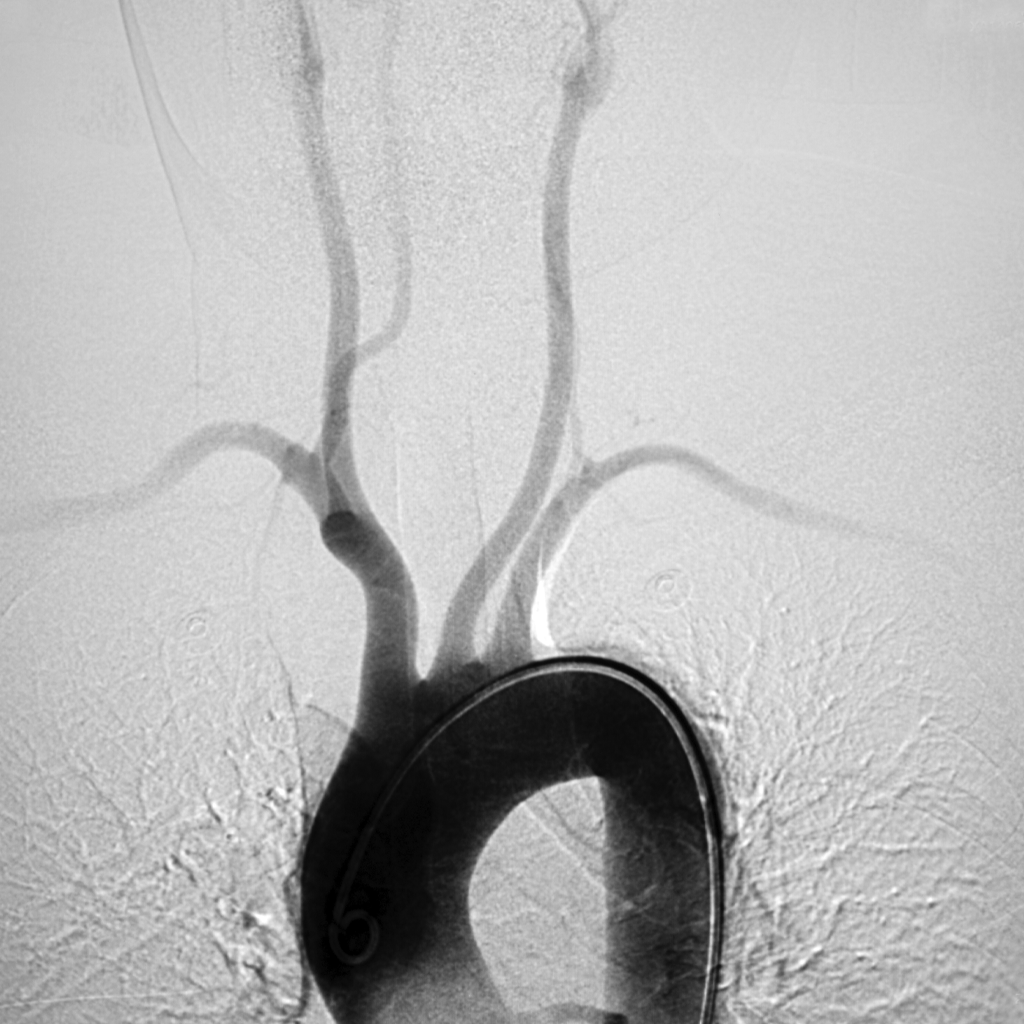

An angiogram is a minimally invasive diagnostic procedure used to visualize arteries and detect blockages or narrowing caused by Peripheral Artery Disease (PAD). Using advanced imaging, our interventional radiologists guide a catheter through a small incision to the affected artery. A contrast dye is injected to highlight blood vessels on X-ray images, revealing any obstructions.

This precise procedure helps identify the extent of arterial issues, guiding effective treatment plans like angioplasty or atherectomy. Performed on an outpatient basis, an angiogram allows quick recovery, helping you return to daily activities with minimal downtime. In many cases, a vascular treatment can be performed during an angiogram.